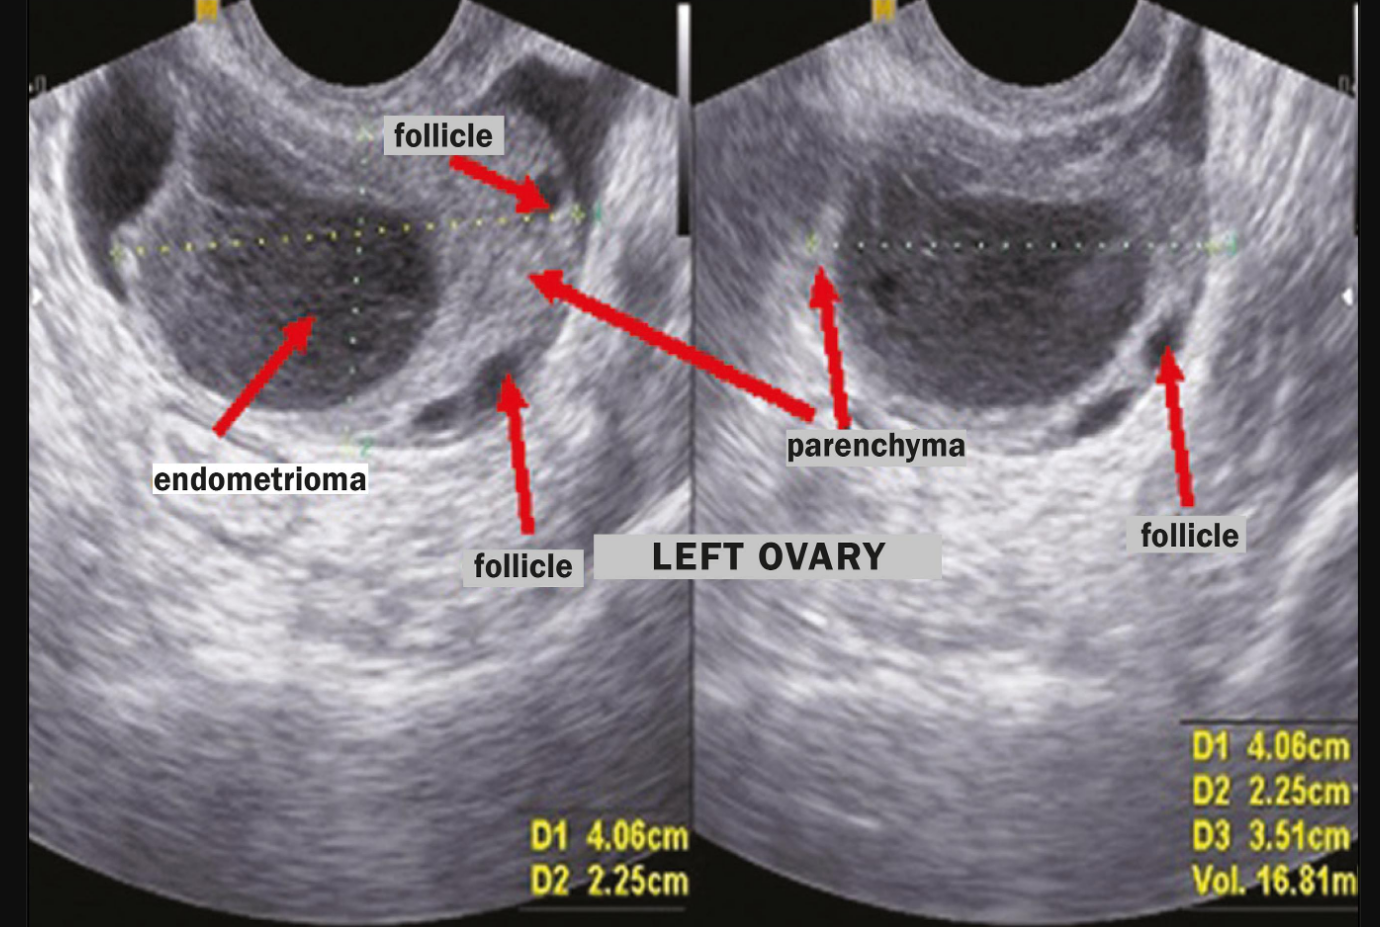

A pelvic examination can be useful for diagnosing endometriosis. The presence of tender areas (nodules) on digital examination or the presence of a pelvic mass are suspicious of a diagnosis of endometriosis. A pelvic ultrasound with a vaginal probe is another excellent diagnostic tool. Ovarian cysts caused by endometriosis (endometrioma) can be seen with ultrasound.